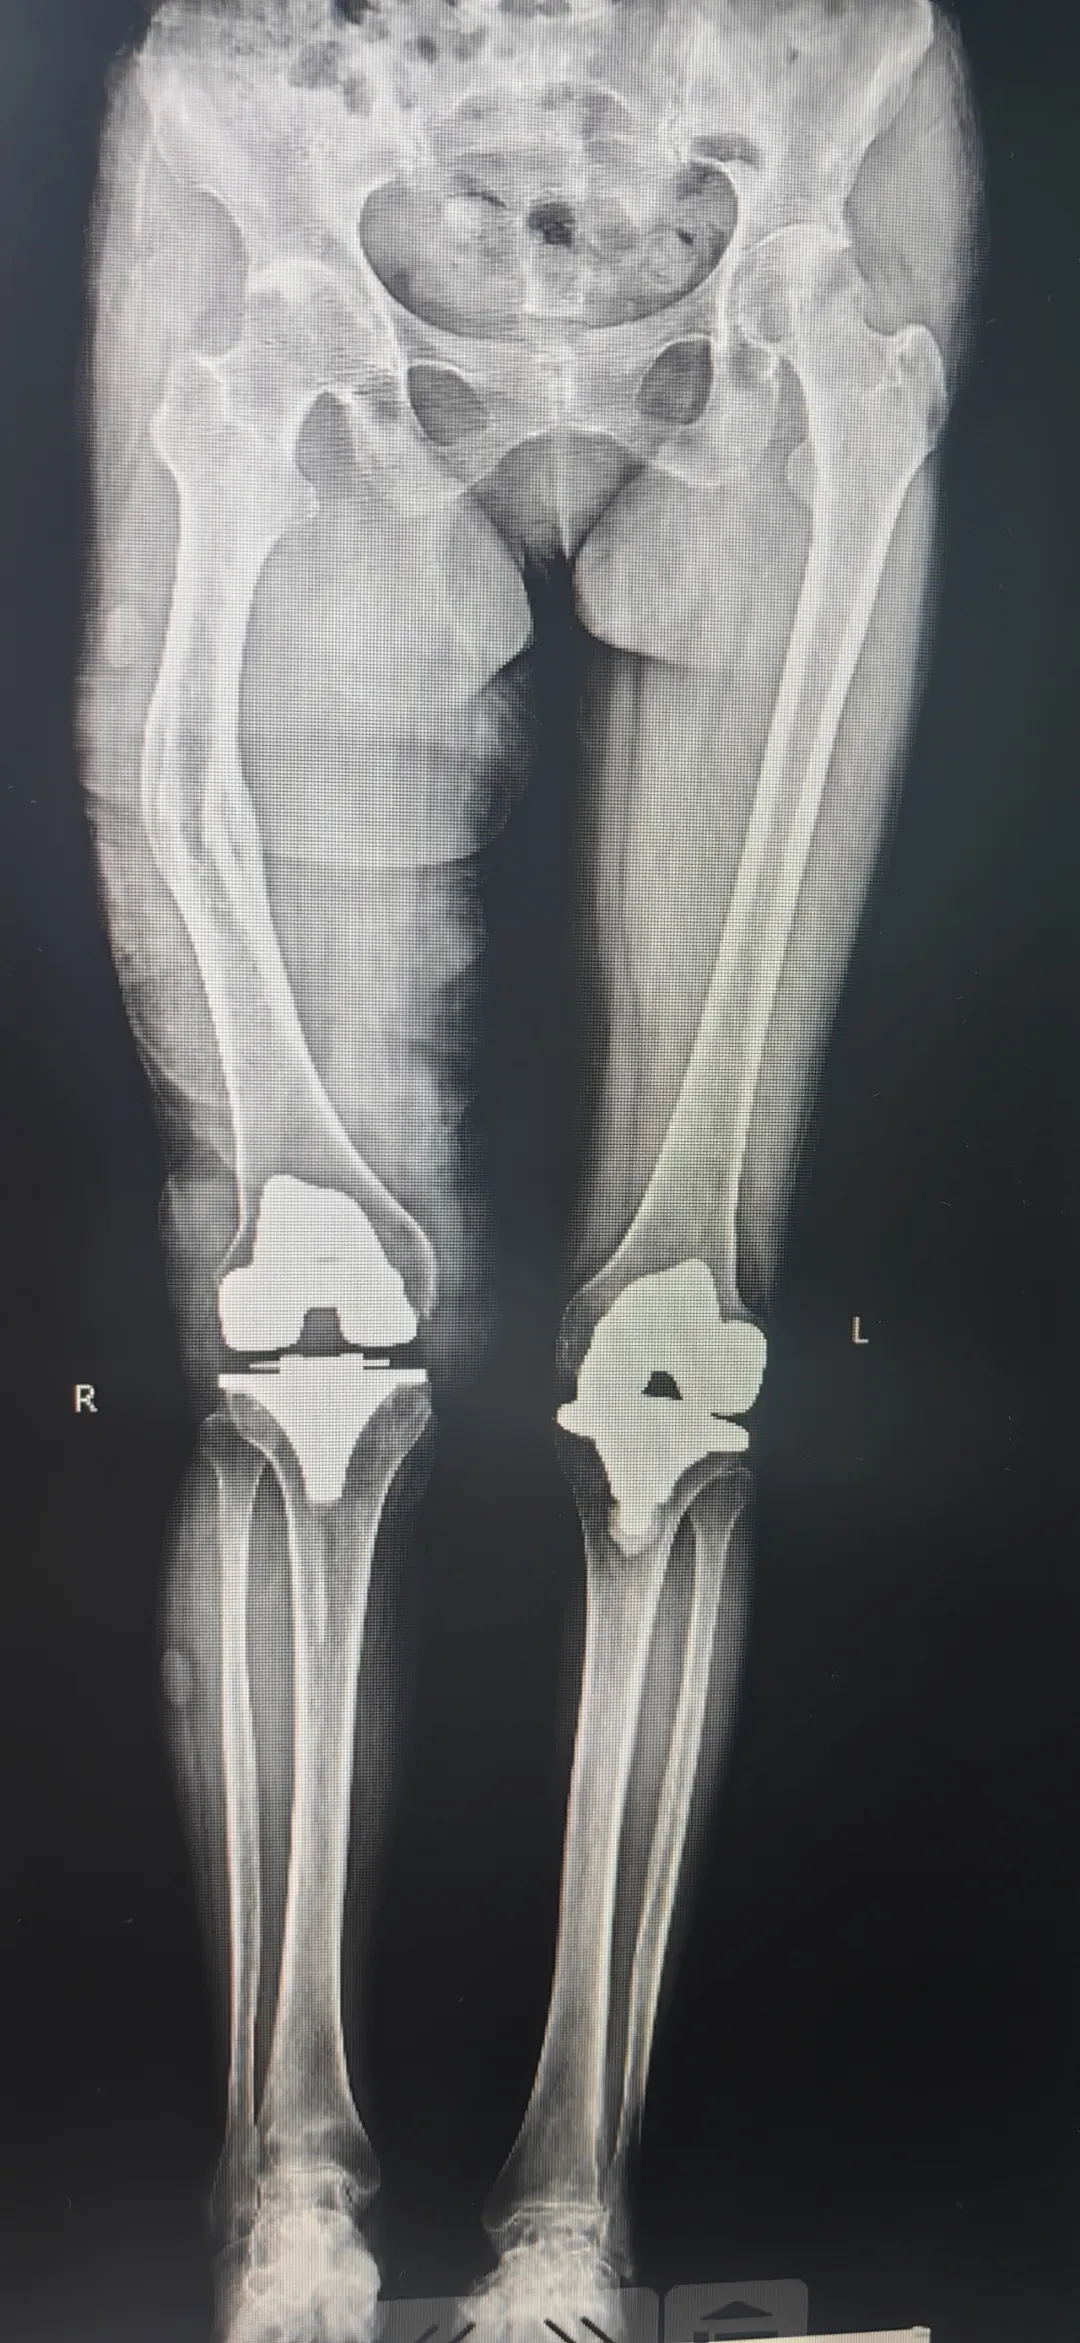

今年59岁的刘女士(化名),患类风湿性关节炎已长达10余年之久。3年前在我院接受了左膝关节置换手术,术后恢复效果显著。近期,她因右膝关节疼痛加剧、活动受限再次就诊。而幼年右侧股骨干骨折的病史,导致其股骨结构畸形,给传统膝关节置换手术带来极大挑战——传统手术依赖股骨髓腔定位截骨,畸形的股骨会直接影响截骨精度,难以保障手术效果,这让患者及家属忧心忡忡。

于是,患者慕名找到我院关节中心1病区李向阳副主任。面对这一复杂病例,李向阳副主任带领医疗团队,依托3D打印技术的精准优势,为患者量身定制诊疗方案。团队通过术前影像数据,打印出与患者股骨近端结构完全一致的3D模型,清晰呈现骨骼解剖细节,精准规划截骨位置、角度等核心参数;同时定制3D打印截骨导板,彻底摆脱传统手术对医生经验的依赖,实现手术操作的标准化、精准化。

右膝关节置换术后X线片